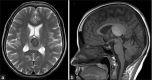

Background: Colloid cysts are usually located at the rostral part of the third ventricle in proximity to the foramina of Monro. Some third ventricular colloid cysts, however, attain large sizes, reach a very high distance above the roof of the third ventricle, and pose some challenges during endoscopic excision. These features led to the speculation that for such a pattern of growth to take place, the points of origin of these cysts should be at areas away from the foramina of Monro at which some anatomical "windows" exist that are devoid of compact, closely apposed forniceal structures.

Results: Colloid cysts may grow vertically up past the roof of the third ventricle through anatomical windows devoid of the mechanical restraint of the forniceal structures.

Conclusion: Some anatomical variations of the forniceal structures may allow unusually large sizes and superior vector of growth of a retro- or post-foraminal colloid cyst. Careful preoperative planning and knowledge of the pertinent pathoanatomy of these cysts before endoscopic excision is very important to avoid complications.